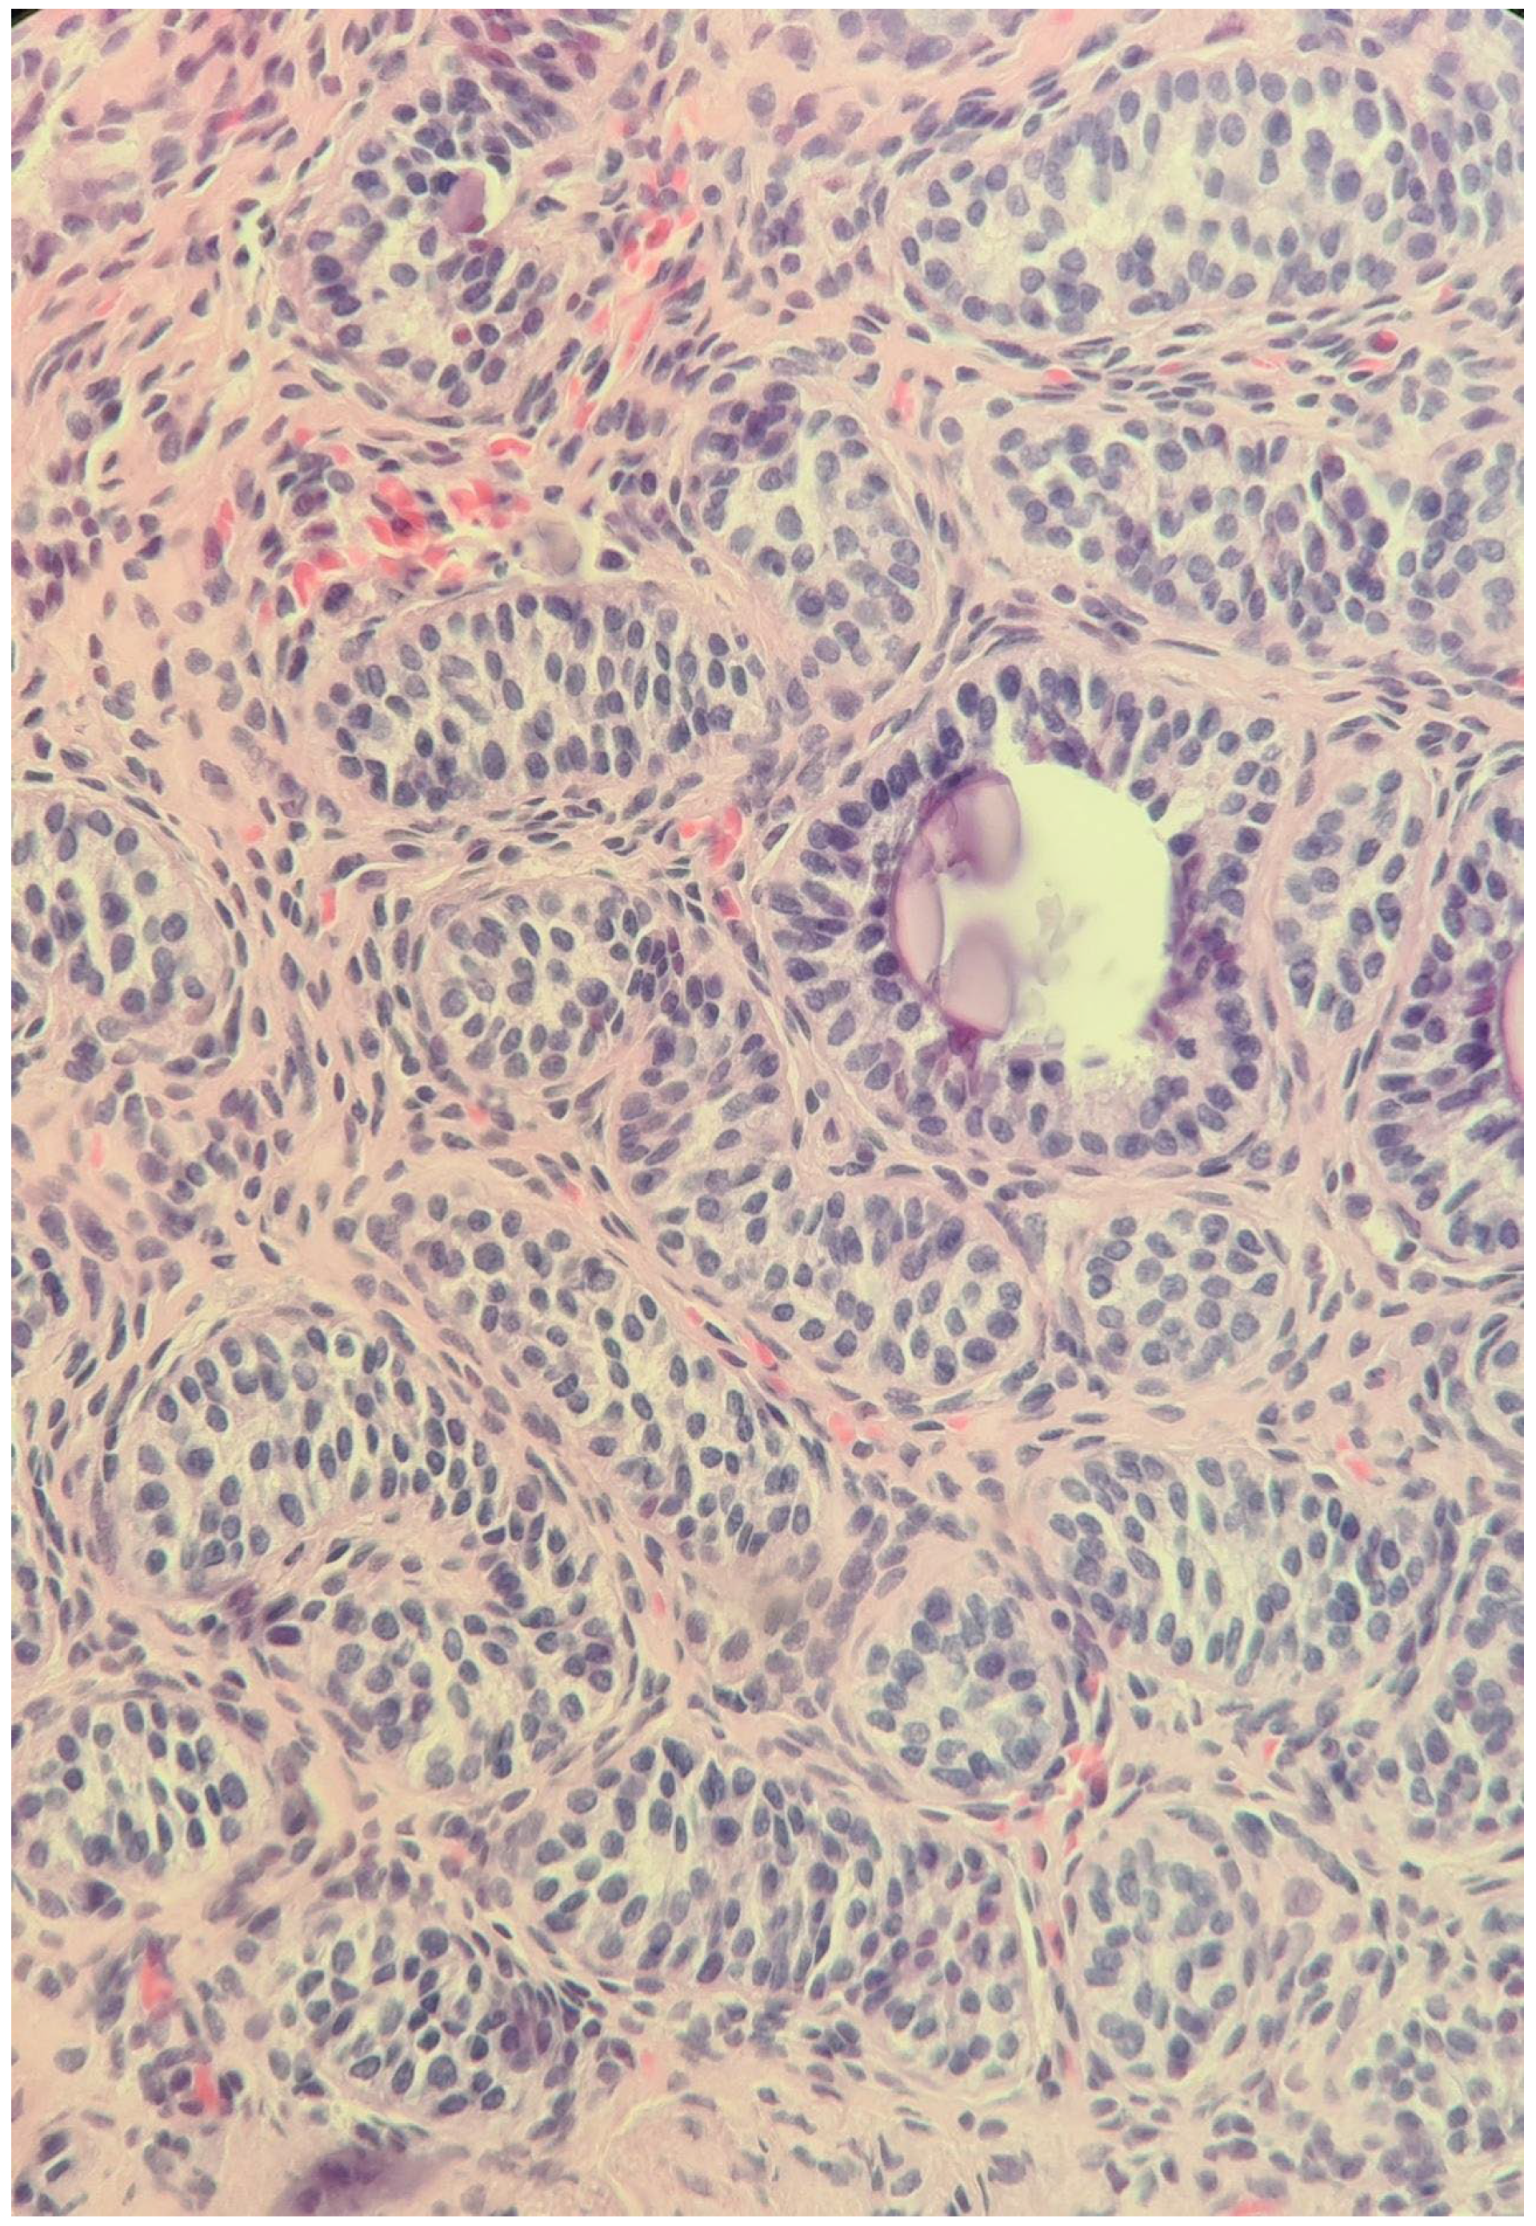

2.4. At Age 13 Years